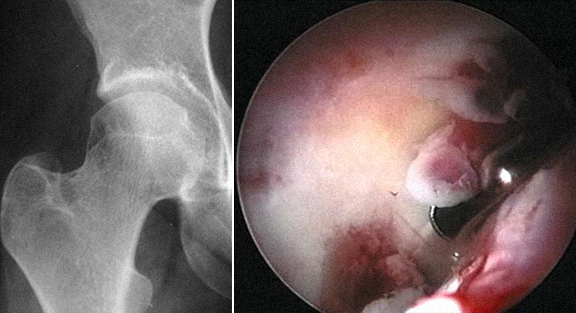

3 - Corpos livres visíveis nas imagens de Rx e TAC, e extração por artroscopia